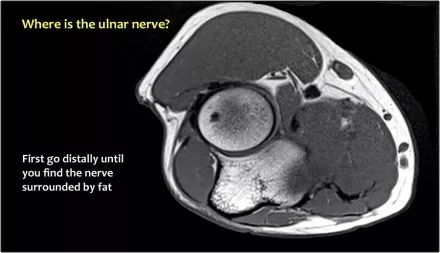

当他们将尺神经带出隧道时,他们把它放在哪里,它可以是皮下,肌肉下或肌肉内。

因此,当我们回到图像时,您会发现很难找到神经。任何这些皮下结构都可以是转位神经。一种方法是远端跟随结构,直到你发现远端的尺神经位于由脂肪包围的前臂近端的正常位置。然后当你向近端跟随它时,你会发现这是皮下移位。

在这种情况下,有神经炎。神经增大。在T2W图像上有高信号。另一个标志是在矢状图像(箭头)上看到的束的不均匀扩大。